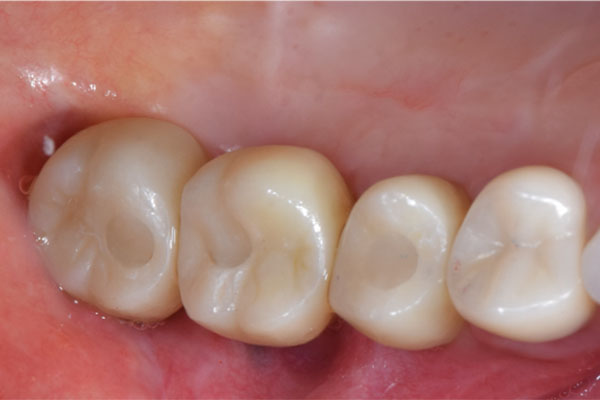

右下の大臼歯部は抜歯後治癒を待ち、骨造成とインプラント埋入を同時に行いました。上部構造はFCZ(ジルコニアセラミッククラウン)となっています。

また左下の親知らずは虫歯のため抜歯、左下7番と5番はセラミックインレー、6番はFCZにて補綴しました。

※FCZ:ジルコニアより少しマイルドな硬さで審美性と機能面に優れているクラウン

全体の治療終了より1年半経過していますが、右下インプラント周囲に骨吸収の像など無く問題なく経過しています。またその他虫歯治療部位や歯の神経治療部位に関しても病変の所見は無く概ね良好と思われます。

治療後、理想的な位置にインプラントが埋入され正しく咬むことができるようになりました。